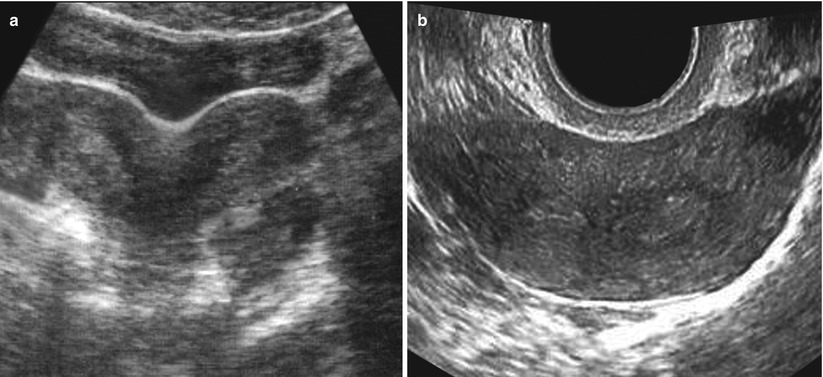

Анатомия женского организма: строение и функции матки